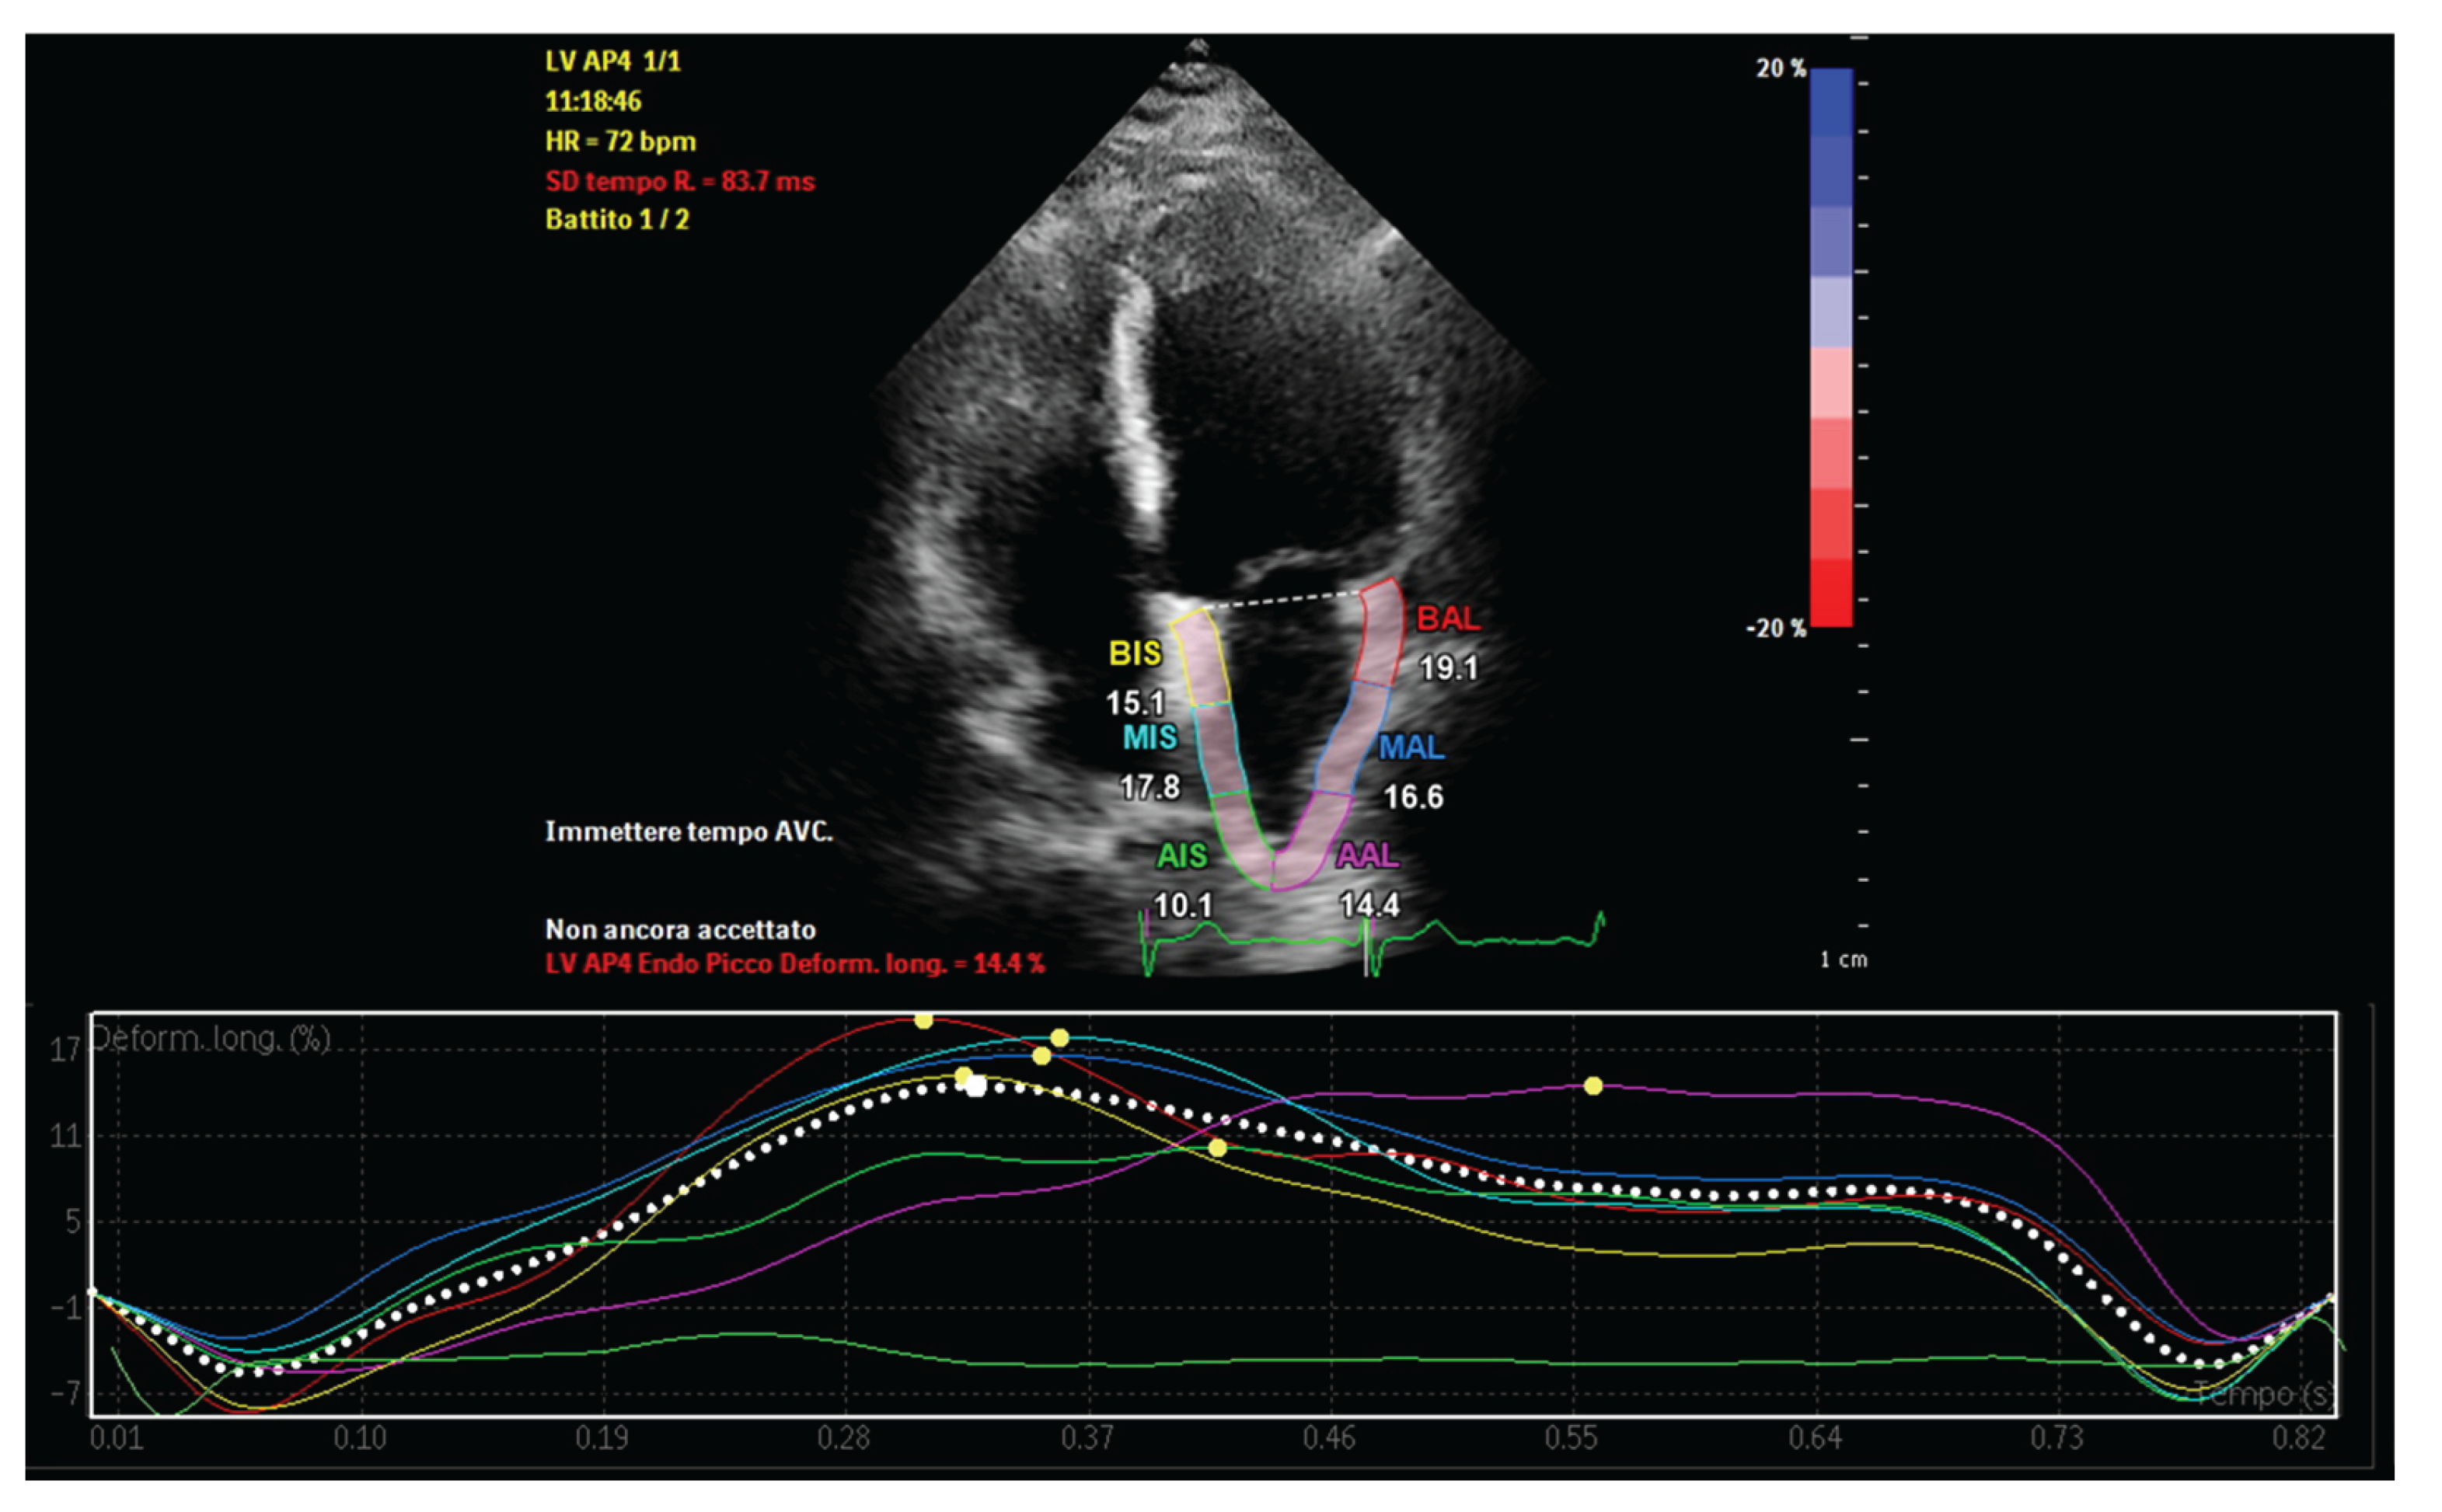

4. Echocardiographic Assessment of Atrial Function in Patients with Increased Epicardial Adipose Tissue

- Cacciapuoti, F; Caso, I; Crispo, S; Verde, N; Capone, V; Gottilla, R; Materazzi, C; Volpicelli, M; Ziviello, F; Mauro, C; et al. Linking Epicardial Adipose Tissue to Atrial Remodeling: Clinical Implications of Strain Imaging. Hearts 2025, 6(1), 3. [Google Scholar] [CrossRef]

- Karsum, EH; Andersen, DM; Modin, D; Biering-Sørensen, SR; Mogelvang, R; Jensen, G; Schnohr, P; Gislason, G; Biering-Sørensen, T. The prognostic value of left atrial dyssynchrony measured by speckle tracking echocardiography in the general population. Int J Cardiovasc Imaging 2021, 37(5), 1679–1688. [Google Scholar] [CrossRef] [PubMed]

- Cacciapuoti, F; Caso, I; Gottilla, R; Minicucci, F; Volpicelli, M; Caso, P. Left Atrial Mechanics and Remodeling in Paroxysmal Atrial Fibrillation: Introducing the EASE Score for Pre-Ablation Risk Prediction. Med Sci (Basel) 2025, 13(3), 131. [Google Scholar] [CrossRef] [PubMed Central]

- Cacciapuoti, F; Gottilla, R; Caso, I; Crispo, S; Pirozzi, C; Minicucci, F; Volpicelli, M. One size does not fit all: Echocardiography as a decision-making tool in atrial fibrillation management – A case series. J Cardiovasc Echography 2025, 35, 403–9. [Google Scholar]